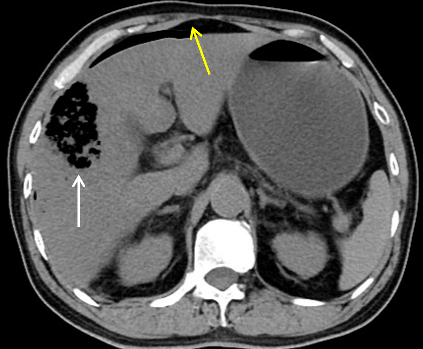

今晨零点左右上厕所后再发畏寒发热,家属发现其口唇发紫、呼吸急促,遂来本院急诊。腹部CT平扫提示肝内积气(图 2)。收住急诊抢救室,急查腹部增强CT,考虑肝脓肿致肝脏破裂(图 3)。

| 图 3 患者冠状位增强CT提示肝内胆管积气(箭头所指处) |